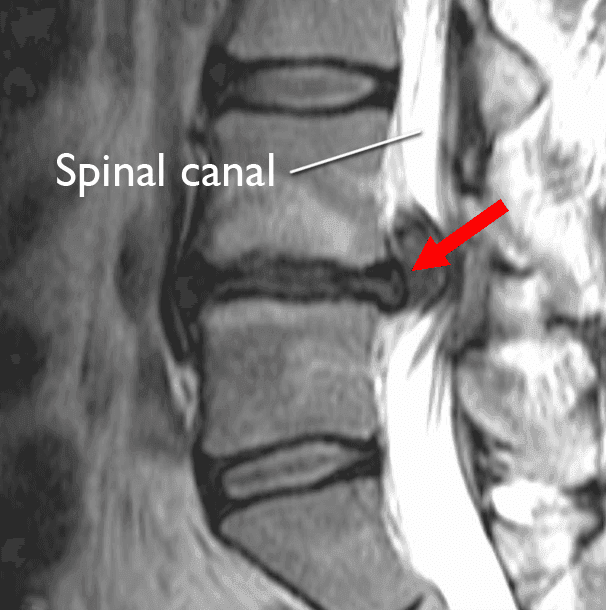

Magnetic Resonance Imaging (MRI) is an invaluable diagnostic tool. MRI scans provide detailed images of soft tissues, allowing for precise identification of herniated discs in the lumbar spine and elsewhere.